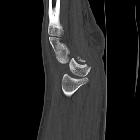

carpal dislocations

Scapholunäre

Dissoziation im Röntgenbild (nicht frisch) bei einem 76-jährigen. Der Abstand zwischen Lunatum und Scaphoid beträgt mehr als 4 mm, was als diagnostisches Kriterium gilt. Wegweisend ist auch der Unterschied zu den anderen Abständen zwischen den Karpalia.